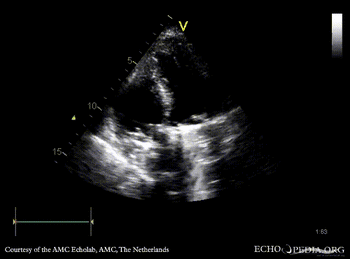

Four prosthetic valves

PLAX: mitral valve prosthesis and aortic valve prosthesis PLAX with Color Doppler